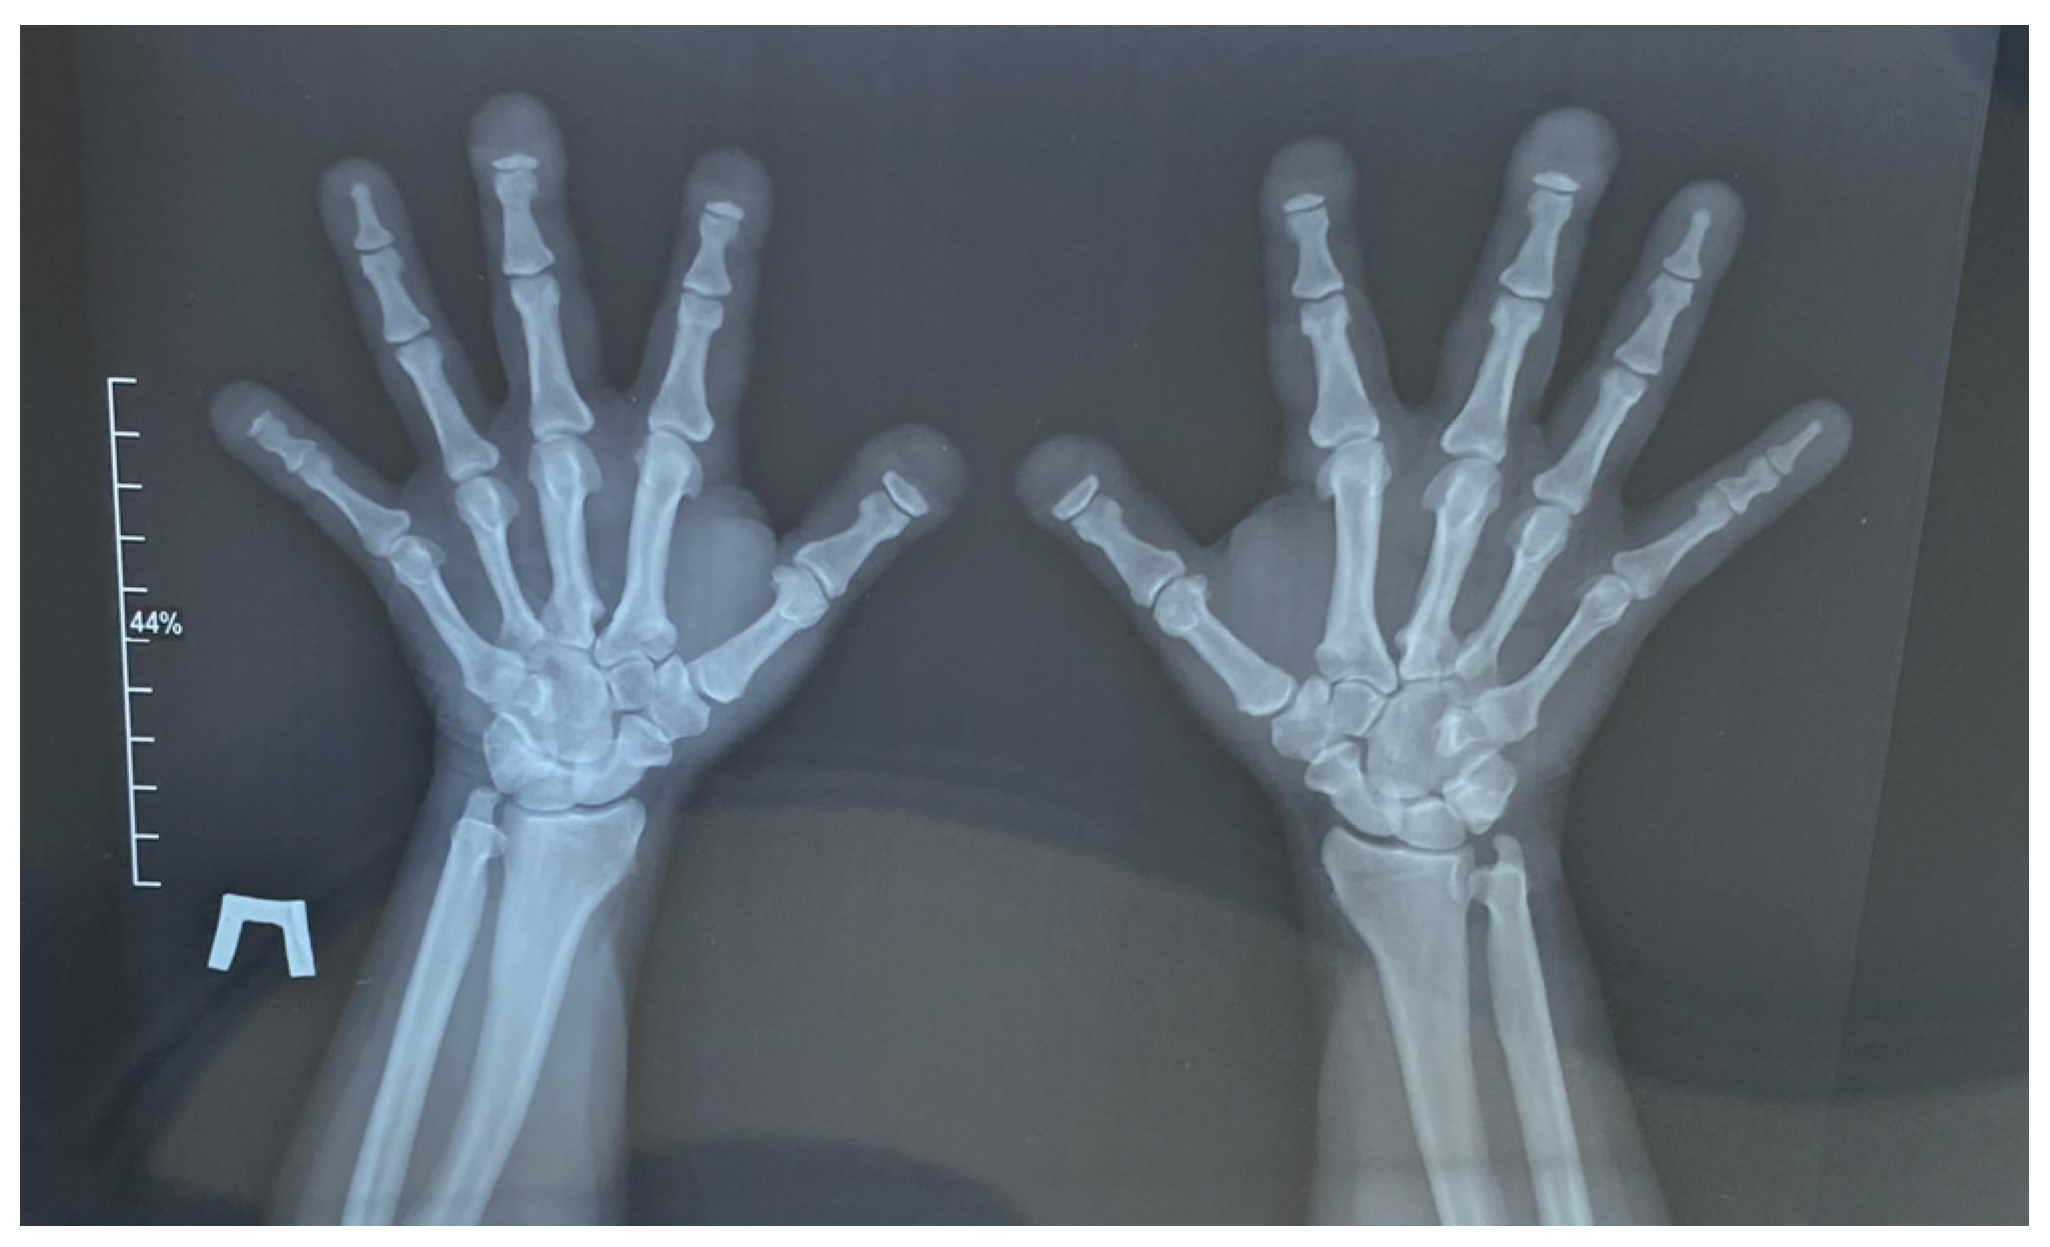

2. Case Presentation